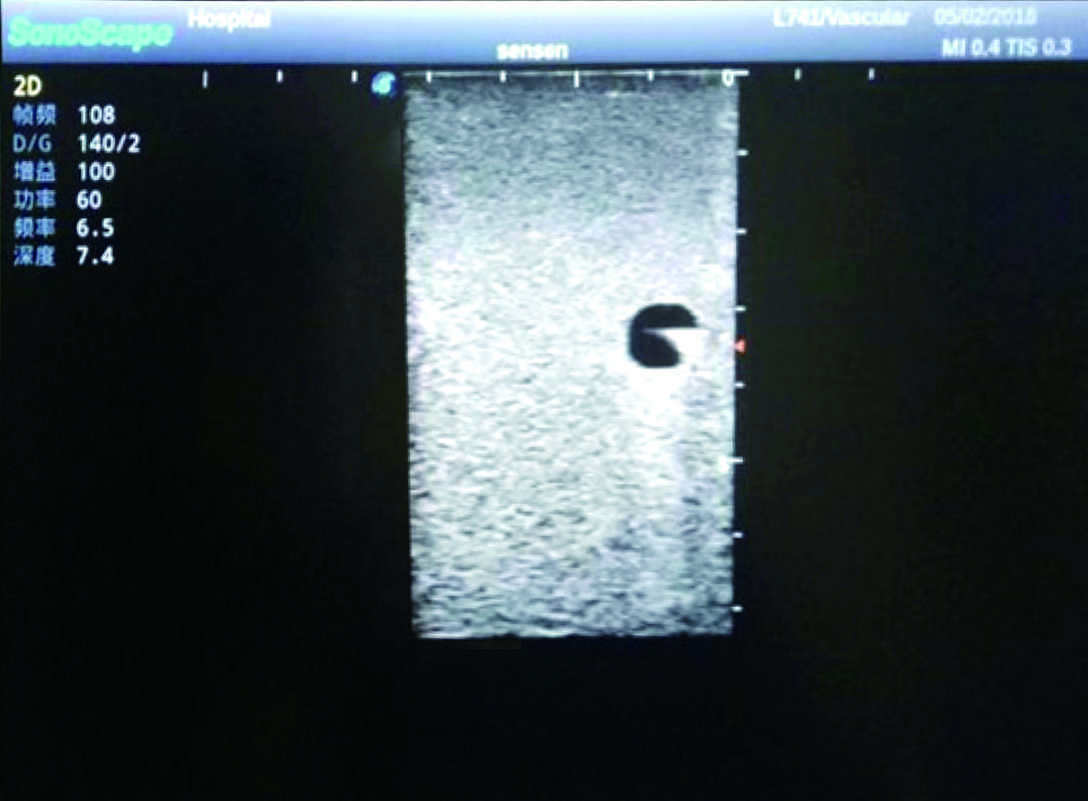

1)   Made of high molecular polymer ultrasound material, close to the real skin

2)   It can be used by real ultrasound machines

3)   Clear and real images of the tissues and organs (basilic vein and superior vena cava)